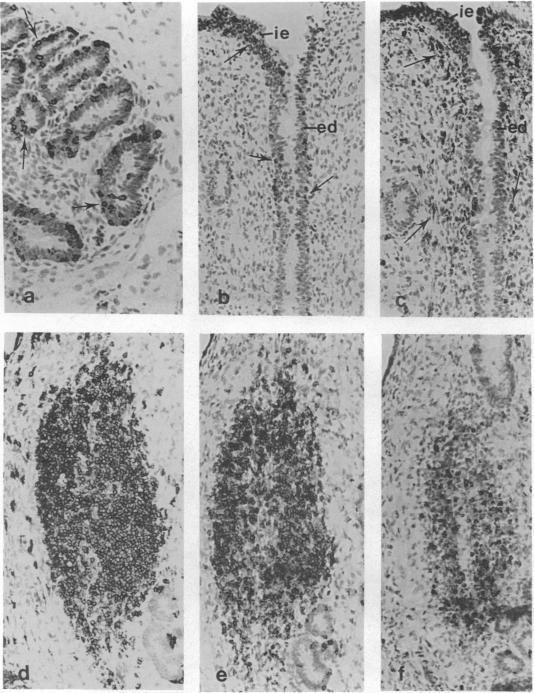

A panel of monoclonal antibodies was used to define the lymphocyte subpopulations in the sheep uterus at various stages of the oestrous cycle. A striking finding was that the majority of lymphocytes in the uterine and endometrial glandular epithelia belonged to a unique lymphocyte subpopulation that expressed the CD45R antigen but was negative for major histocompatibility complex (MHC) class II molecules and expressed low or undetectable levels of the CD5 antigen. When examined under the electron microscope using the immunogold technique, the CD45R+ lymphocytes were found to have one to three membrane-bound granules in their cytoplasm. Other lymphocyte subpopulations found in the uterus at various stages of the oestrous cycle were localized mainly in the caruncular and intercaruncular stroma. The unique CD45R+ granular lymphocyte subpopulation may be equivalent to the 'natural killer' cells reported in mouse and man, and may have an important role in local immunity of the female reproductive tract.

一组单克隆抗体被用于确定发情周期不同阶段绵羊子宫中的淋巴细胞亚群。一个显著的发现是,子宫和子宫内膜腺上皮中的大多数淋巴细胞属于一个独特的淋巴细胞亚群,该亚群表达CD45R抗原,但主要组织相容性复合体(MHC)II类分子呈阴性,且CD5抗原表达水平低或检测不到。当使用免疫金技术在电子显微镜下检查时,发现CD45R+淋巴细胞的细胞质中有一到三个膜结合颗粒。在发情周期不同阶段子宫中发现的其他淋巴细胞亚群主要位于肉阜和肉阜间基质中。独特的CD45R+颗粒淋巴细胞亚群可能等同于在小鼠和人类中报道的“自然杀伤”细胞,并且可能在女性生殖道的局部免疫中发挥重要作用。